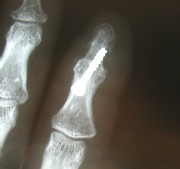

Middle and right: stiffening in the functional position with the V-tek regular screw. Eliminates pain and visually shows a satisfying result.

Below: End-joint stiffening in the index finger and middle-joint endoprosthesis in the middle finger